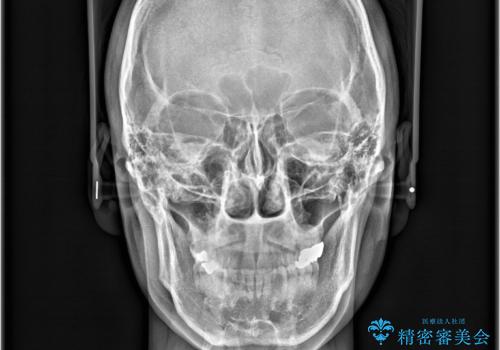

歯の隙間とデコボコ、シザーズバイトも改善され、咬み合わせや見た目が整い、患者様にも大変ご満足いただけました。